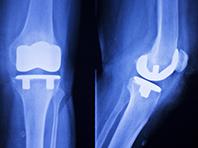

Углеродная замена суставов готова штурмовать рынок

Уникальные углеродные имплантаты для исправления дефектов скелета человека презентовала госкорпорация Ростех, передает Ремедиум. По словам разработчиков, отечественные имплантаты будут в 1,5-2 раза дешевле иностранных аналогов из металла и керамики. Также,...